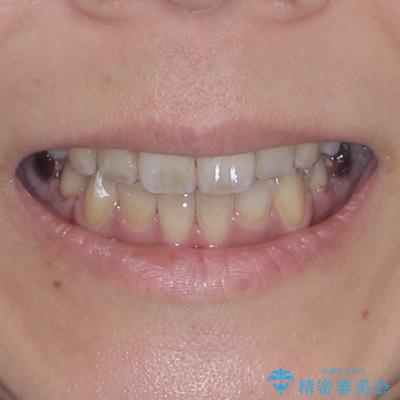

デコボコと口元の突出感 ハーフリンガルでの抜歯矯正

- 前歯のデコボコと上顎の前突感による口の閉じにくさを気にして来院された患者様です。

目立たない装置を希望されたので、上顎が裏側装置のハーフリンガルを選択し、上下左右の小臼歯(計4歯)を抜歯して矯正治療を行うこととしました。

表側のワイヤー矯正に比べると治療期間は長く、費用も高額となりますが、どうしても目立たせたくないという方にはお勧めの抜歯矯正です。